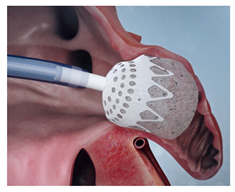

(Photo courtesy Conformal Medical) | CLAAS [81] Conformal Medical | PCUU foam matrix surrounding nitinol endoskeleton; enhanced conformity; atraumatic surface, due to foam folding at distal edge. | Limited to two sizes; may not cover full spectrum of LAA anatomies; long-term efficacy and safety data still being collected. |